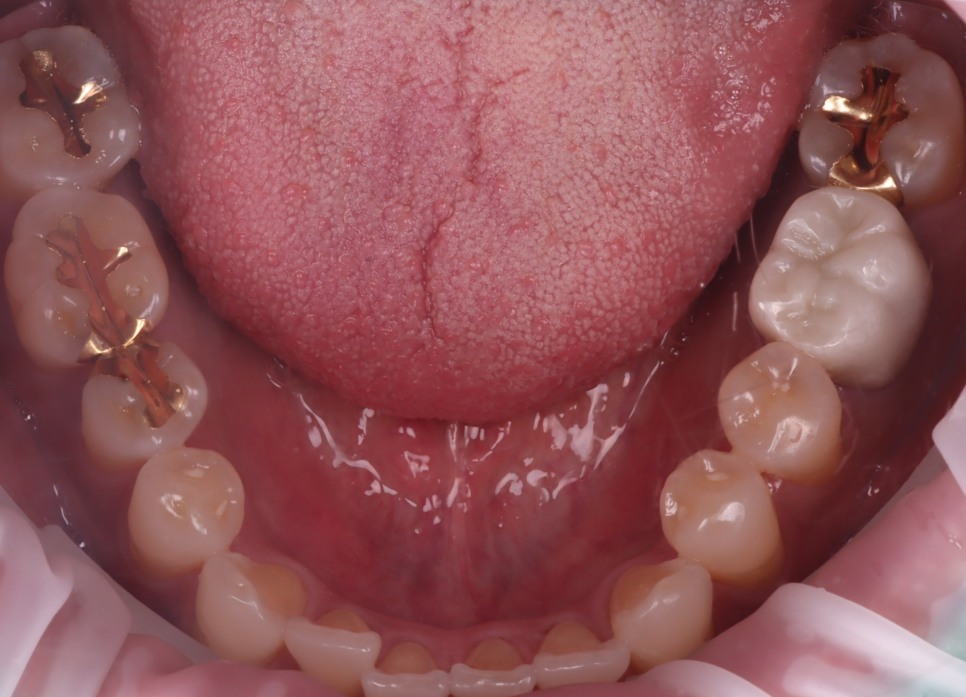

촬영일 : 250908

보철은 E-max 오버레이를 택했어요.

전체를 깎아 씌우는 풀 크라운 대신

필요한 면만 골라 감싸는 방식이에요.

촬영일 : 250915

프렙 시에도 건강한 벽은 남겨 페룰

(지렛대에 버티는 테두리)을 확보했고

임시치로 씹는 높이와 동요를 체크한 뒤

최종 보철은 레진 시멘트로 완전히 접착했어요.